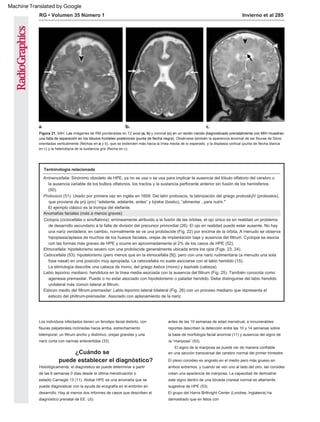

Variante interhemisférica media La

variante MIH, descrita por primera vez por Barkovich

y Quint (46) en 1993, es un subtipo clínico-

neurorradiológico distinto de HPE (18) (Figs. 20, 21).

El diagnóstico fetal es posible (47,48).

En el espectro de HPE alobar a lobar, el área más

severamente no separada es el cerebro anterior basal,

mientras que en MIH, son los lóbulos frontal posterior y

parietal los que no se dividen (19). Espectáculos de imágenes

de los lóbulos frontales "fusionados". Puede verse en

con el diagnóstico prenatal de HPE lobar versus SOD (45).

Figura 20. MIH. Imágenes axiales de RM semi-Fourier ponderadas en T2 obtenidas a las 33 semanas de edad gestacional estimada. Nótese la falta de

separación de la línea media en las áreas frontal posterior y parietal (*), mientras que las regiones rostral y posterior del cerebro están divididas normalmente

y las órbitas están espaciadas normalmente. Además, tenga en cuenta las fisuras de Silvio orientadas verticalmente (flechas), que se conectan de manera

anormal a través del vértice.

falta de separación de la línea media en las áreas frontal

posterior y parietal, mientras que las áreas más polares del

cerebro normalmente están divididas. En el desarrollo paralelo,

normalmente se forman la rodilla y el esplenio del cuerpo

calloso, pero el cuerpo está ausente (19). Las fisuras de Silvio

en pacientes con MIH a menudo están orientadas verticalmente

y anormalmente conectadas a través de la línea media sobre el

vértice del cerebro (19). Se observa que dos tercios de los

pacientes con MIH tienen displasia cortical o materia gris

heterotópica subcortical (19), y se encontró un quiste dorsal en

el 40% (18). Las características distintivas entre HPE lobar y

MIH son la ubicación de la disgenesia callosa (genu y tribuna en

HPE lobar versus cuerpo en MIH) (16) y el área de no separación

hemisférica descrita anteriormente.

Figura 21. MIH. Las imágenes de RM ponderadas en T2 axial (a, b) y coronal (c) en un recién nacido diagnosticado prenatalmente con MIH muestran

una falta de separación en los lóbulos frontales posteriores (punta de flecha negra). Obsérvese también la apariencia anormal de las fisuras de Silvio

orientadas verticalmente (flechas en a y b), que se extienden más hacia la línea media de lo esperado, y la displasia cortical (punta de flecha blanca

en c) y la heterotopía de la sustancia gris (flecha en c).